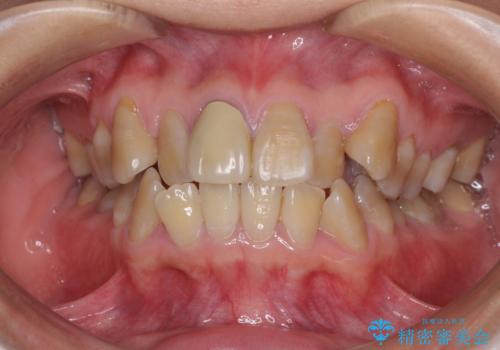

- 八重歯や前歯のデコボコを気にして来院された患者様です。

歯列が前方に傾斜しており、デコボコが強かったため、上下左右第一小臼歯4歯を抜去し、ワイヤー装置による矯正治療を行うこととしました。